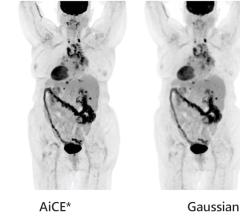

September 15, 2022 — University of Minnesota Twin Cities scientists and engineers have found a way to improve the ...